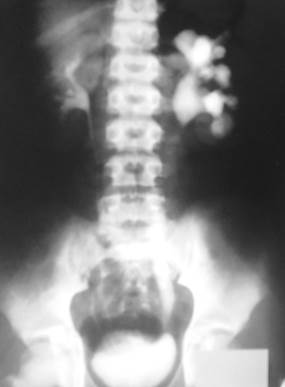

Инструментальное обследование (см. рисунок):